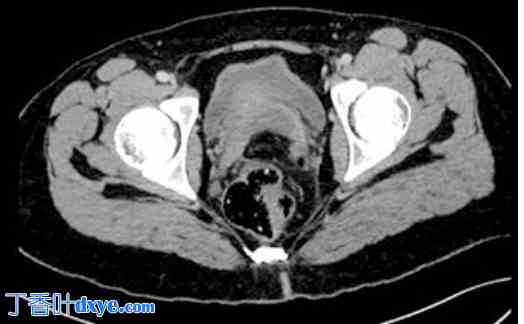

诊断评估:血液检查显示生物炎症综合征,伴有白细胞增多(15200个/立方毫米,C反应蛋白水平升高至65毫克/升)。脂血症和β-HCG水平正常。胸腹CT扫描显示腹腔内中等量游离积液,盆腔腹膜片增厚,但无气腹(图1)。CT扫描还显示少量炎性淋巴结。阑尾无肿大,卵巢呈多卵泡状(图2)。胸部CT扫描显示双侧基底实质实变,并伴有充气支气管征,与双侧基底肺炎相符。

图2.

阑尾在CT扫描中显示正常